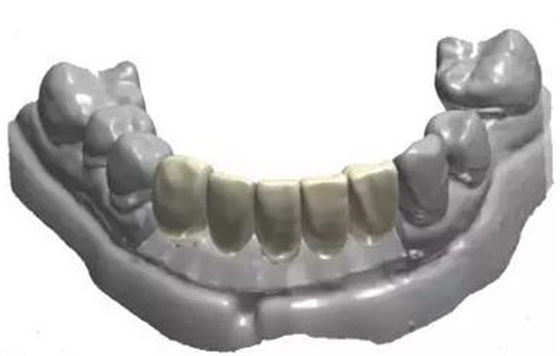

利用3shape導(dǎo)板軟件虛擬排牙

以修復(fù)為導(dǎo)向規(guī)劃植體

牙支持式導(dǎo)板生成

通過3Shape Dental System軟件同期設(shè)計(jì)臨時(shí)冠

手術(shù)導(dǎo)板數(shù)據(jù)發(fā)送至成都登特,通過BEGO打印機(jī)打印出導(dǎo)板,切削出臨時(shí)冠